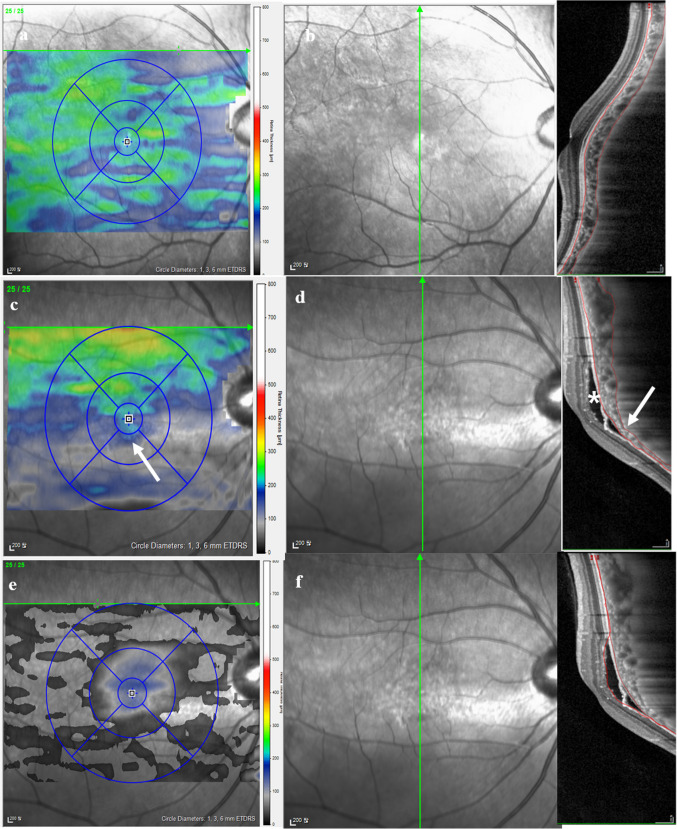

Purpose: To investigate the morphological characteristics of dome-shaped macula (DSM) and inferior staphyloma complicated by serous retinal detachment (SRD).

Methods: Electronic medical records and multimodal images of patients diagnosed with DSM and inferior staphyloma were retrospectively reviewed. Morphological features, including axial length, curvature height, orientation of the dome, presence of retinal pigment epithelial detachment, choroidal vascular features such as subfoveal choroidal thickness, variations in choroidal thickness, presence of abrupt changes in choroidal thickness and presence of large choroidal vessels were analyzed.

Results: Fifty-three eyes of 37 patients were included, of which 33 eyes had DSM and 20 eyes had inferior staphyloma, and 15 (28.3%) were complicated with SRD. Four (12.1%) of the DSM and 11 (55.0%) of the inferior staphyloma eyes had SRD. On univariate analysis of risk factors for SRD, shorter axial length (p = 0.002), presence of inferior staphyloma (p = 0.004), higher subfoveal curve height (p = 0.009), thicker subfoveal choroidal thickness (p = 0.038), greater variation in choroidal thickness (p = 0.005), presence of both abrupt changes in choroidal thickness (p < 0.001) and large choroidal vessels (p = 0.001) showed a significantly higher risk. On multivariate analysis, shorter axial length (p = 0.038) and presence of abrupt changes in choroidal thickness (p = 0.008) were identified as significant risk factors for SRD.

Conclusion: SRD was more prevalent in eyes with inferior staphyloma compared to DSM. Shorter axial length and abrupt changes in choroidal thickness were associated risk factors for SRD.